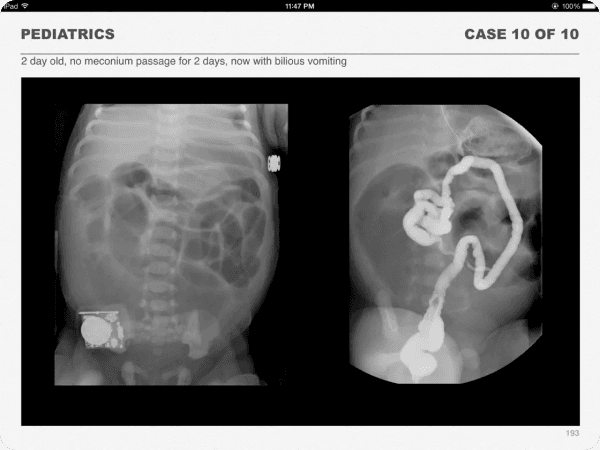

One-hundred classical cases with diagnostic-quality images are included in the clinical section of the book.